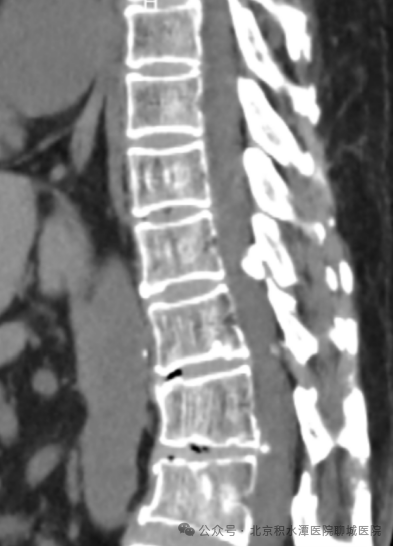

术前影像:C5/6椎间盘向左后方突出,压迫神经根

术前影像:T11/12胸椎黄韧带骨化,胸椎椎管狭窄